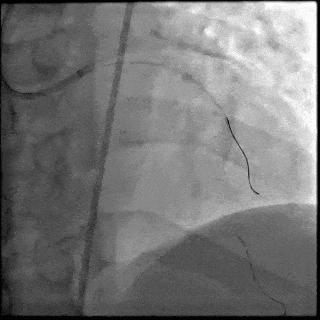

【DSA图2.前降支支架释放】

5月28日8:00,葛均波院士团队在中山医院16号楼16楼中伟厅成功连线喀什二院导管室,沪喀远程手术正式开始。8:35,新疆喀什二院导管室内股动脉入路通路建立后,行左右冠脉造影示左前降支中段存在85%的严重狭窄,狭窄位于血管分叉路口且紧邻心肌桥;且左回旋支中段近乎闭塞,血管细窄且迂曲,病变弥漫。8:59,葛院士于上海操控血管介入机器人主端PANVIS COF,将指引导管送至左冠脉开口,并操控主支导丝和分支血管保护导丝通过狭窄病变,后送至前降支和对角支血管远端以建立轨道,同时利用介入机器人的微速调整功能避开心肌桥,以亚毫米级精准定位释放1枚支架。在成功处理患者左前降支病变后,葛院士通过搓捻机械操纵杆,远程精细调整导丝“进攻”方向,顺利通过左回旋支次全闭塞病变。因血管相对细小且病变弥漫,葛院士决定采用单纯球囊扩张术处理,即刻造影提示几乎无残余狭窄,避免了额外的支架植入。10:10,撤出所有导丝及导管,手术顺利结束。